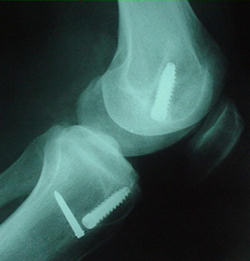

Planlamada önceki kesiler, kullanılan implantlar, ilk tünellerin yeni açılacak tünellerle ilgisi değerlendirilmeli, ilk implantların çıkartma setleri bulundurulmalıdır. İlk tüneller çok genişlemiş ve yeni greftin yerleşimini ve tespitini engelliyorsa iki seanslı cerrahi gerekli olabilir. İlk seansta implantlar çıkartılır ve tüneller greftlenir, sonra ikinci seansta revizyon cerrahisi yapılır. Bunun için oto veya allogreft hazırlığı olmalıdır. Revizyonda kullanılacak tendon grefti seçimi önemlidir. Hastada daha önce kullanılmayan otolog greft kaynakları ilk tercih olmalıdır. Bu mümkün değilse karşı diz ya da allogreft tercih edilebilir.Cerrahi teknik

Revizyon cerrahisi diz ekleminin artroskopisi ile başlar. İlk cerrahideki greft artıkları temizlenir, eşlik eden meniskal ve kondral patolojiler düzeltilir. İlk cerrahi sırasında kullanılan implantlar, yeni tünelleri engellemiyorsa çıkartılmamalıdır. Özellikle yeni tünele yakın olan implant çıkartılırsa, tünel duvarları zayıflayabilir. Tibial tarafta çoğunlukla daha medialden bir tünel açılabilir.

Tünel genişlemesi varsa, büyük kemik bloklu allogreft veya greftleme sonrası iki seanslı cerrahi düşünülmelidir. Femoral tünel ilk cerrahide çoğunlukla önde açıldığı için arkaya ve inferiora doğru ikinci bir tünel mümkündür. Standart tespit yöntemlerine ek olarak eklemden uzak ilave tespit yöntemleri gerekli olabilir. Genişlemiş tünellerde eklemden uzak tespit yapılırsa, tünel içinde hareketi azaltmak için biyoçözünür vida veya kemik grefti eklenebilir.